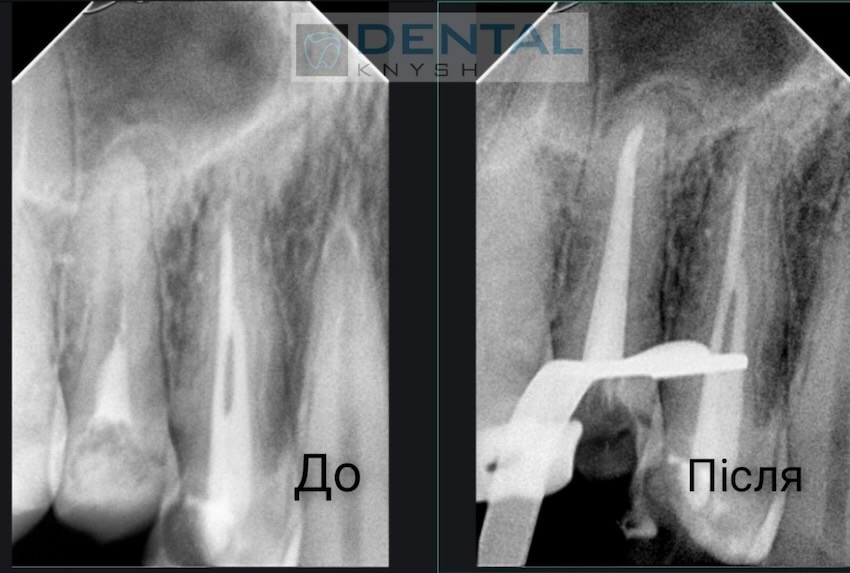

Лікар-ендодонтист Вадим Петриченко спеціалізується на лікуванні зубних каналів під мікроскопом.

Фото звіти

Більше фото звітів можна подивитися на сторінці Лікування зубів під мікроскопом